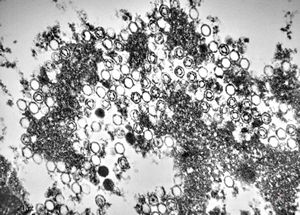

M,50y. | Pneumocystis carinii - lung